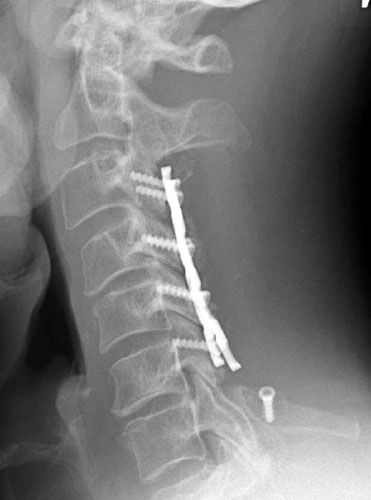

AP and lateral radiographs taken 5 days later, while still in the

hospital. Note migration of left C6 screw. It has loosened and fallen out. This

screw was not causing symptoms and decision was made to conservatively manage

the patient and keep in rigid cervical collar until the bone graft matured in

2-3 months. |